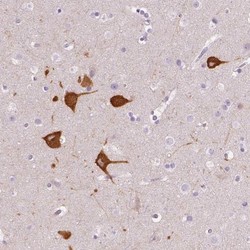

Supportive validation

- Submitted by

- Novus Biologicals (provider)

- Main image

- Experimental details

- Immunohistochemistry-Paraffin: FAM163B Antibody [NBP2-57157] - Immunohistochemical staining of human cerebral cortex shows cytoplasmic positivity in neuronal cells.